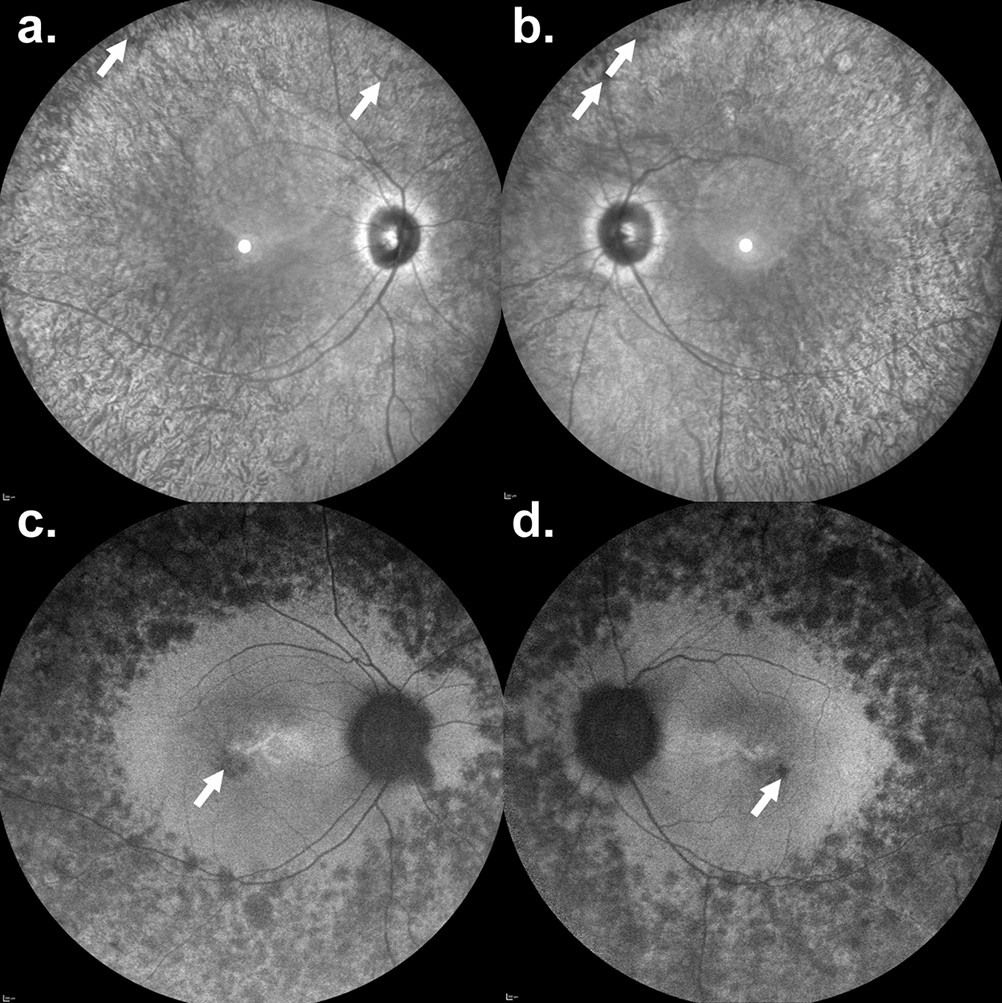

Figure 2

A 34-year-old man with a retinitis pigmentosa phenotype carrying a homozygous AIPL1 c.364G>A (p.G122R) variant. Nyctalopia since early childhood was described by the patient. Visual acuity was 20/50 in the right eye and 20/100 in the left eye. (a,b) Infrared reflectance imaging. The retinal vessel diameters are reduced with bone-spicule-like pigmentation in the peripheral retina (white arrows). Fundus autofluorescence revealed multiple hypoautofluorescent spots within the peripheral retina. There was no macular ring of increased signal, but small hypoautofluorescent lesions were seen within the fovea (white arrows).